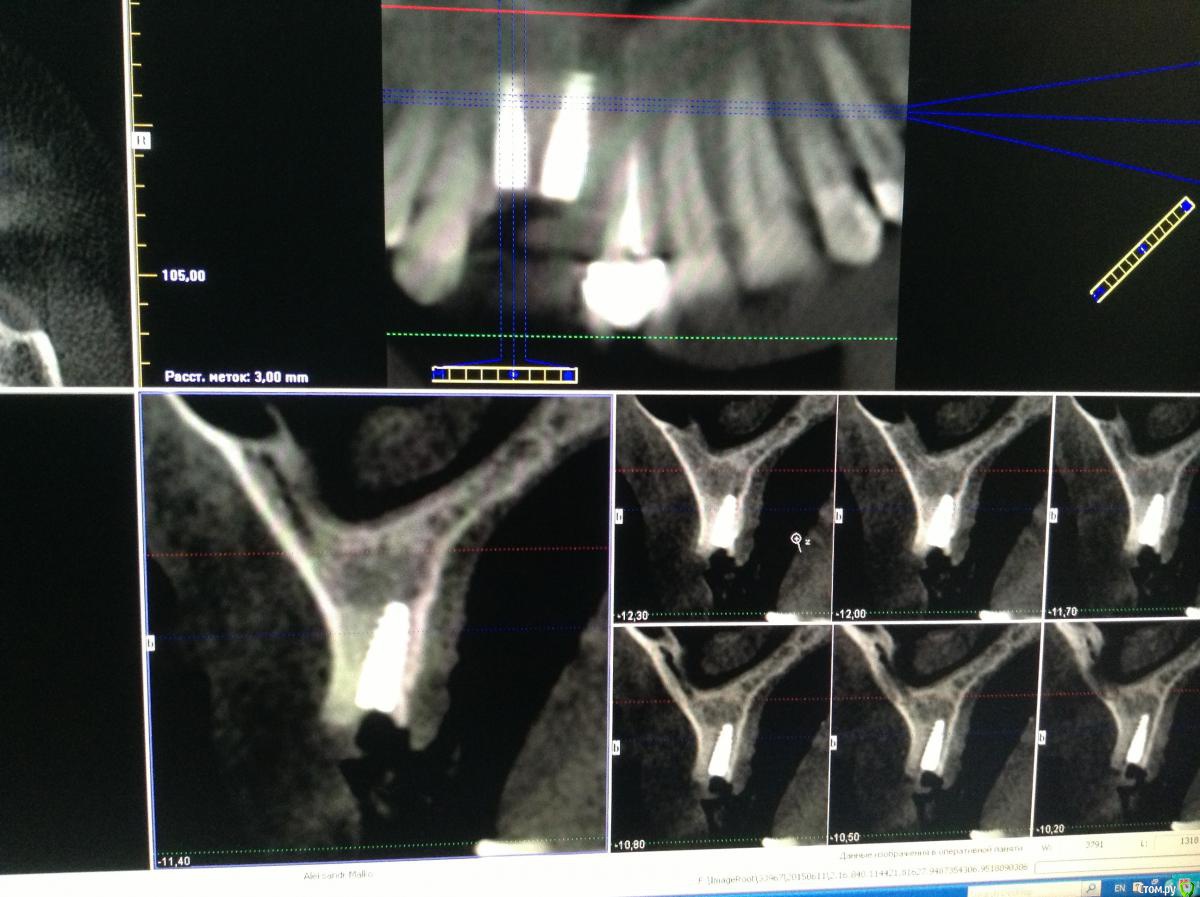

Pro100Andre Опубликовано 10 июля, 2015 Автор Поделиться Опубликовано 10 июля, 2015 Вот так получилось 12 терапевты не решились перелечивать Ссылка на комментарий

zzkz Опубликовано 10 июля, 2015 Поделиться Опубликовано 10 июля, 2015 фото во рту покажите?мне кажется близко др к др. и может пострадать сосочек. А может срез такой Ссылка на комментарий

JIM Опубликовано 12 июля, 2015 Поделиться Опубликовано 12 июля, 2015 Какой тут может быть сосочек??? Рецессии бы не было!Удачи оператору и пациенту Ссылка на комментарий